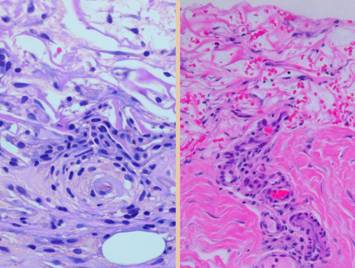

Left upper, the forearm contracture shown in a previous panel.  Integra was used to reconstruct skin after first excising the contracted scar.  Late results show no scar, no scar hypertrophy, no contractures.  Left lower, a keloid excised from behind the ear, skin then reconstructed preemptively with Integra to prevent recurrent keloid.  Late photo shows the area healed with no signs of scar hypertrophy.  Right, a pane of comparative histology.  Top row shows normal dermis, one view having been cut parallel to skin tension lines, the other orthogonal.  Whether seen on side or on end, normal dermis with normal elasticity and has an architecture of collagen bundles separated or porated with interstitial spaces which give it some deformability and pliability, typically greater in one direction than the other.  Middle row shows young scar and young Integra.  The scar is dense in collagen, no spaces, no opportunities for shifting and rolling of bundles, all oriented into locally thick bands but without an overall uniform direction, making the scar anisotropically stiff.  In comparison, young Integra has local fibrous foci which are separated from each other by the matrix, thereby maintaining interstitial porosity and the ability of domains to shift or distend relative to each other, a configuration and mechanics much more like normal dermis.  Bottom row shows scar and Integra in phases of late maturation after many years.  Both have remodeled away from their original appearance back toward normal dermis or fascia,  The difference is that young scar quickly becomes packed with immobile excessively dense collagen, and then it takes years to remodel back to normal stromal density, architecture, and mechanics.  Integra-CGM also takes years to remodel back to a strictly normal appearance, but it has the fundamental architectural and mechanical features of normal dermis right from the very beginning.

Left, a microscope image of normal wound healing.  The structure shown here is the prototypical wound.  Details of the structure and process will be explained in following panels.  Right, the microscopic appearance of fully regenerated Integra-CG matrix, the details likewise to be explained in following panels.  Even without explaining or focusing on specific details, the dissimilarity of the two can be appreciated.  Angiocytes and fibroblasts, vessels and connectives – that is all there is to these two tissues.  However, by supplying different “rules” or “subroutines” for the interaction and assembly of these elements, two different biomaterials emerge.  The rules or routines are based on the circumstances, reaction-to-injury versus embryonic regeneration.  The results have very different physical properties and implications for daily life, functional adaptations, and potential need for ongoing medical care.